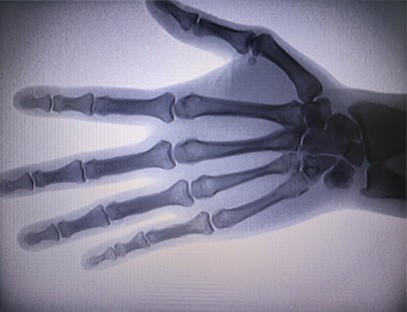

ایک پورٹیبل ایکسرے مشینتابکاری کی کم خوراک ہے، انتہائی محفوظ پورٹیبل آلہ جو تابکاری کی نمائش کو کم کرتے ہوئے اعلیٰ معیار کی تصاویر حاصل کرسکتا ہے۔ یہ ہسپتال کے بڑے آلات کی خامیوں کی تلافی کرتا ہے اور اسے کسی بھی وقت منتقل اور لے جایا جا سکتا ہے۔ خاص طور پر ان اکائیوں اور افراد کے لیے موزوں ہے جن کا بجٹ ناکافی ہے اور تصاویر کے لیے کم تقاضے ہیں۔ ہماری نئی نسل کی ایکسرے مشین 10 انچ کی ہائی ڈیفینیشن بڑی اسکرین سے لیس ہے، جس میں دیکھنے کے زاویے کی حد زیادہ ہے اور یہ پوری ہتھیلی کو مکمل طور پر دیکھ سکتی ہے، بشمول فریکچر، ڈس لوکیشن، گٹھیا، اور ہڈیوں کے ٹیومر۔ آرتھوپیڈک فلموں کو پرنٹ کرنے کے لیے اسے فلم پرنٹر سے منسلک کیا جا سکتا ہے، اور اسے صنعتی پیداوار اور جانچ کے لیے بھی استعمال کیا جا سکتا ہے۔ تاریک کمرے، براہ راست نقطہ نظر، حقیقی وقت کے مشاہدے کی ضرورت نہیں ہے۔ اس مشین میں ہائی ریزولوشن امیجنگ سسٹم ہے جو ہڈیوں کے کسی بھی ڈھانچے کی تصاویر کو بہت واضح طور پر کھینچ سکتا ہے۔ طبی، پالتو جانوروں، صنعتی، الیکٹرانک مصنوعات کے مینوفیکچررز، معائنہ اور دیکھ بھال کے محکموں، اور تحقیقی لیبارٹریوں کے لیے بہترین ایکسرے ٹیسٹنگ کا سامان اور حل فراہم کرنا۔

تخصص:آرتھوپیڈک کلینک کی ضروریات کے لیے ڈیزائن کیا گیا ہے، خاص طور پر کے لیے موزوں ہے۔ایکس رے امیجنگاعضاء جیسے ہاتھ، کلائی، کہنیاں، کندھے، گھٹنے، ٹخنے وغیرہ۔

واضح امیجنگ:اعلیٰ درجے کی ڈیجیٹل امیجنگ ٹیکنالوجی کا استعمال اعلیٰ معیار کی ایکس رے تصاویر فراہم کرنے کے لیے کیا جاتا ہے، جس سے ڈاکٹروں کو حالت کی درست تشخیص میں مدد ملتی ہے۔